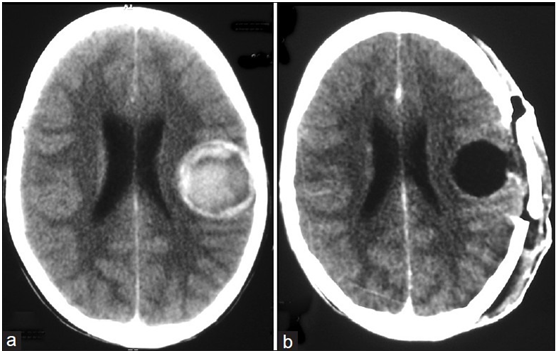

一名13岁男性儿童,有多次全身性强直阵挛性癫痫发作及头痛持续三个月之病史。没有局灶性虚弱的病史。他的全身检查很正常。从神经学上讲,他是有意识的,警觉的,对时间、地点和人有方向感。脑神经正常。运动和感觉检查正常,无局灶性神经功能缺损。血液检查正常。CT平扫大脑可见界限清楚的病灶(大小4.2×4.5 cm),位于左侧颞顶区内侧高密度区,呈团块效应[图1a]。根据这些发现,诊断海绵状血管瘤与癫痫发作。患者行左颞顶骨开颅术,包括周围胶质组织在内的病灶完全切除[图1b]。这名儿童在一年的随访中表现良好,没有任何癫痫复发。

图1 :(a) CT平扫显示左侧颞顶区病灶清晰,有出血迹象;(b) CT随访显示完全切除